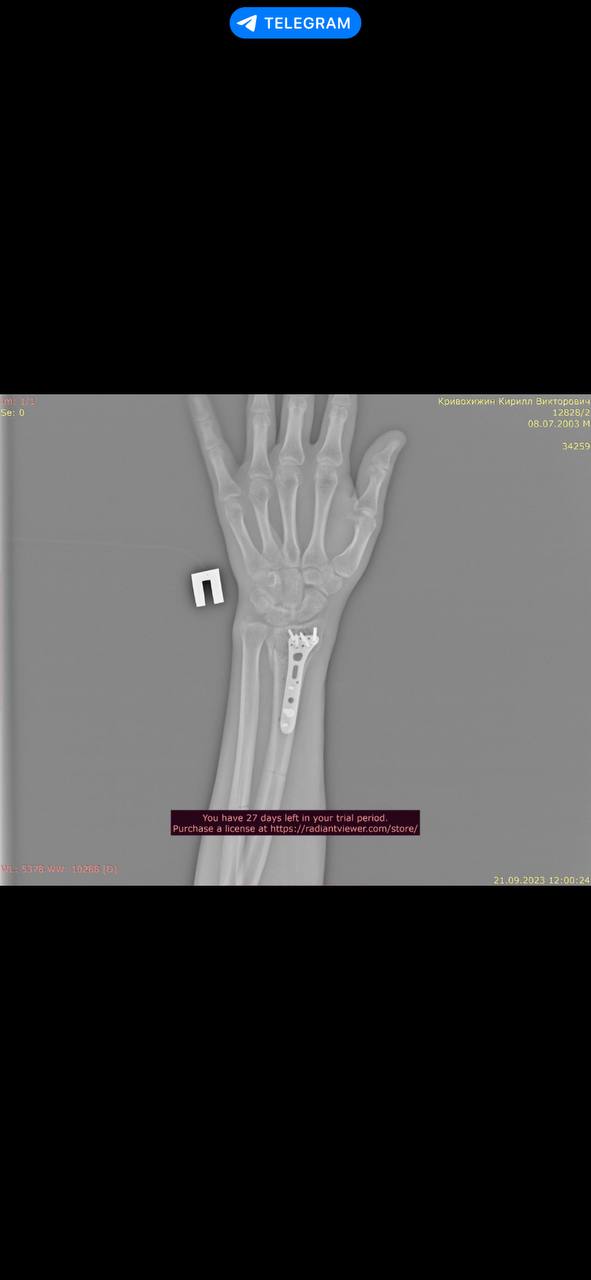

2 года назад получил тяжелые травмы, в результате чего мне установили металлоконструкции в плече и локте левой руки и в луче правой руки.

Снимки трех металлоконструкций прилагаю. Их не удалял и удалять не планирую.

P.S Кисть на левой руке разгибается максимум на 50 градусов из 90.